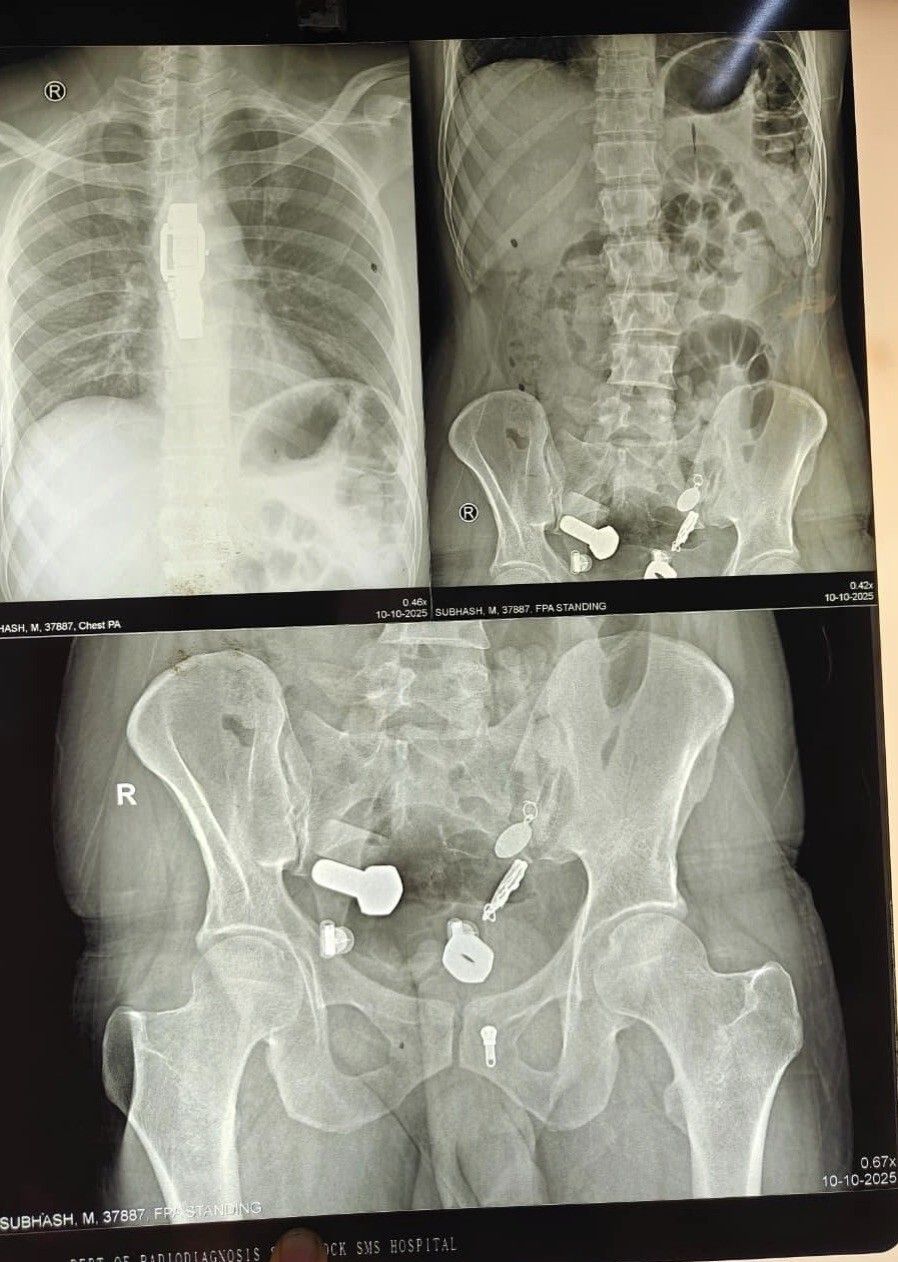

Родственники привезли 34-летнего мужчину в больницу, когда он почувствовал сильную боль в животе и не мог есть и пить. Сканирование показало, что в его пищеводе застряли часы, а в толстом кишечнике оказались металлические фрагменты, гайки и болты.

Врачи обнаружили целую коллекцию в животе пациента.Хирурги попытались удалить предметы с помощью эндоскопии, но потребовалась полостная операция, она продлилась три часа.

Через небольшой разрез в брюшной полости хирурги извлекли часы и другие инородные тела.Мужчина поступил в больницу Саваи Мансингх в Джайпуре, Индия, 9 октября. Сейчас он восстанавливается.